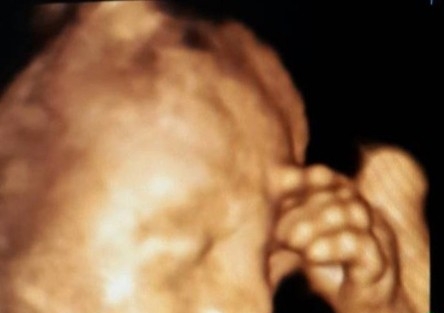

Anne Karnında Düşünen Bebek